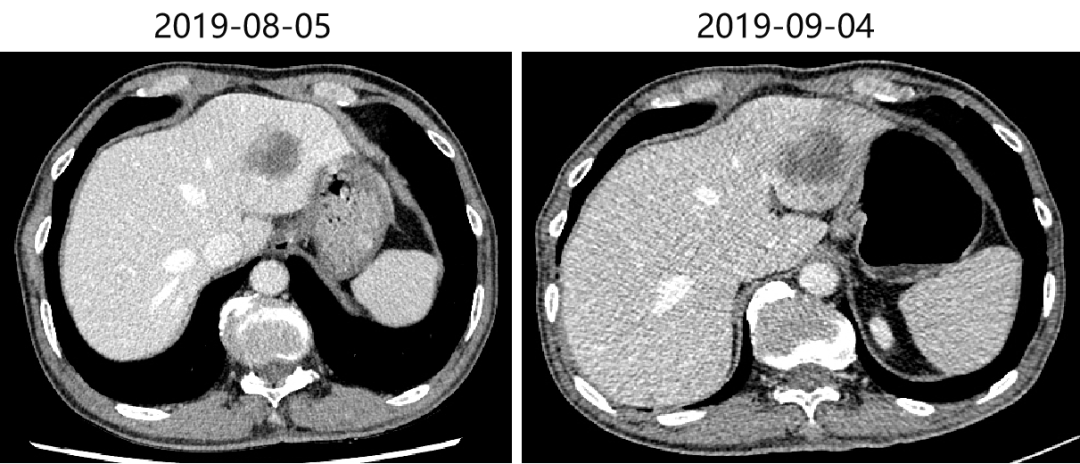

2019-08-05 胸腹部增强CT提示:双肺多发结节影,部分考虑转移可能,建议抗炎治疗后复查;双上肺肺气肿,多发肺大疱;脊柱胸段S形侧弯;胃术后改变;肝脏多发囊肿;肝左叶占位,考虑转移;胆囊结石;左肾小囊肿;前列腺钙化;直肠管壁局部增厚,考虑直肠癌可能,建议结合肠镜活检。

肝:肝左叶占位,考虑转移。

2019-09-04 [CT]示:双肺下叶结节,较前(2019-08-05)相仿,恶性可能大;双肺多发结节,较前相仿,转移可能;直肠K术后,胃术后,请结合临床;肝左叶占位,较前增大,考虑转移。

肝:肝左叶占位,较前增大,考虑转移。